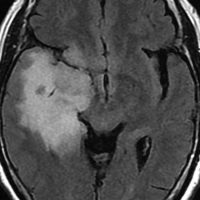

良性の乏突起膠腫の巨大なもの

これは30歳くらいの若い女性にできた乏突起膠腫です。軽いけいれん発作を生じましたがその後は無症状です。上がT2強調画像で,下がガドリニウム増強像です。CTでは石灰化が散在していました。大脳深部をほとんど埋めるように腫瘍は浸潤して広がっています。脳外科の先生にこの患者さんが無症状だといっても信じてもらえないのですが本当です。

ほんの少しだけ腫瘍をとって(生検術)病理診断を確定しました。

腫瘍が大きすぎるので,認知機能を保つために,全脳照射30グレイとテモゾロマイド化学療法を2年しました。以来9年以上たちますが,とても頭の良い方でちゃんと働いておられます。

この患者さんから学ぶことはたくさんあります。この広範に伸展した腫瘍はおそらく10歳前後から存在したのだと想像されます。腫瘍が発見されず未治療だったからこそ,これまで通常の生活ができたのかもしれません。

また,グレード2の乏突起膠腫には限りなくグレード1に近い高分化型の腫瘍が存在するということです。乏突起膠腫は手術で完全摘出できれば治るのでしょうが,手術によって認知機能障害や高次脳機能障害を生じれば社会生活を一人ですることは難しくなります。分化型の乏突起膠腫は,正常の神経細胞や脳機能を破壊しないで浸潤増大しますから,脳の中にこんなに広がっても,何の症状も出さないということがあります。同じグリオーマでも膠芽腫などと比べれば大きな差があるのです。治療後の生存の質を考える時に,このような例があるということを思い出すことは大切です。